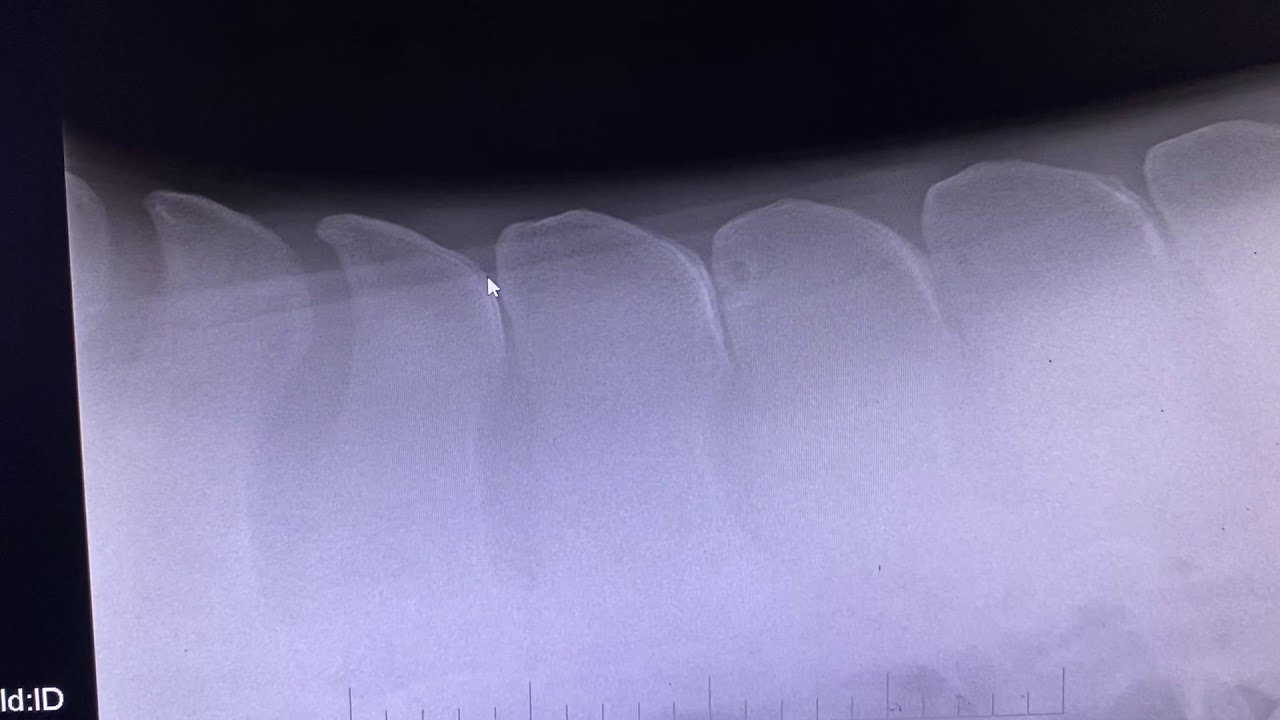

Kissing Spine Surgery YouTube

REHABBING MY HORSE FROM KISSING SPINE SURGERY The Lispy Rider YouTube

ODSP Surgery Kissing Spines Equine Surgery B W Equine Hospital

WE FINALLY HAD KISSING SPINE SURGERY The Lispy Rider YouTube

JET S KISSING SPINE SURGERY VLOG JEDS EQUINE YouTube

JET S KISSING SPINE SURGERY Rehab Part 1 Post op Recovery And

ODSP Kissing Spine Surgery Bandage Change B W Equine Hospital YouTube

Kissing Spine Surgery In Horses Honnas Technique YouTube